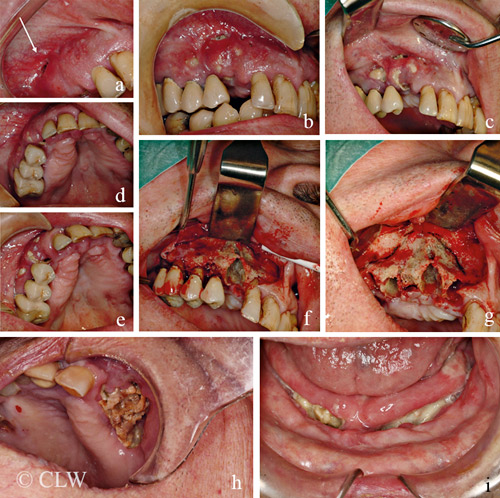

Figur 1 visar en typisk manifestation av käkbensnekros. Den är vanligast i underkäken (2/3 av fallen) men hos ca 8–10 procent av patienterna är båda käkarna drabbade. Käkbensnekros kan vara inducerad av ett mekaniskt trauma såsom skav från en illapassande tandprotes eller en avtryckssked för krona, bro eller protes hos tandläkaren, eller skada av ett laryngoskop i samband med intubation vid generell anestesi [9].

De flesta patienterna uppvisar endast ett fokus med exponerat käkben, medan några enskilda patienter utvecklar stora och multipelt utbredda områden med nekrotiskt ben i båda käkarna (Figur 1). Riskpatienter som behandlats med titanimplantat för ersättning av en eller flera tänder kan riskera att förlora implantaten efter några år med efterföljande nekrotiska lesioner (Figur 1). Hos andra patienter förekommer endast svullnad och smärta men även lösa tänder och dålig andedräkt, vilka är ganska ospecifika symtom men som kan diagnostiseras som käkbensnekros med hjälp av radiologiska fynd och PAD.

Figur 1. Bild a–g: En 68-årig man med prostatacancer med spridning till skelettet har fått behandling med en intravenös injektion av 4 mg zoledronsyra var 4:e vecka under 3 års tid och utvecklat käkbensnekros i överkäken som sträcker sig från kindtandsområdet fram till hörntanden, som lossnat spontant. Patienten är rökare och har parodontit (tandlossning). a) Initialt ses en liten fistel i omslagsvecket. b) d) Efter antibiotikabehandling minskar symtomen och svullnaden, och det nekrotiska käkbenet blir mer synligt. c) e) Efter ytterligare 3 veckors antibiotikabehandling sticker tydliga bensekvestrar ut genom slemhinnan. f) Vid friläggning ses den tomma alveolen efter hörntanden och det nekrotiska käkbenet. g) Tänder är avlägsnade och det nekrotiska området som planeras att avlägsnas är avgränsat med en linje. Bild h: En patient med osteoporos, insulinbehandlad diabetes och ca 10 års behandling med alendronsyra, veckotablett (70 mg), har utvecklat käkbensnekros på vänster sida i överkäken med direkt kommunikation in till sinus maxillaris. Bild i: En patient med osteoporos, polymyalgia rheumatica och tidigare ovarialcancer har fått behandling med kortikosteroider och alendronsyra, veckotablett (70 mg), under ca 5 års tid. Titanimplantat installerades i underkäken för att ersätta förlorade tänder, men efter ett år lossnade alla implantaten och patienten utvecklade en avancerad käkbensnekros i underkäken.